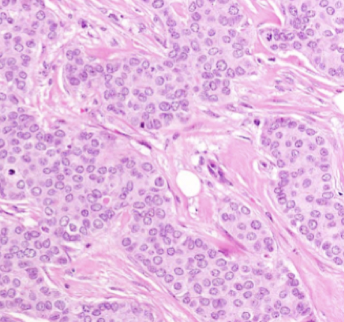

Core biopsy - normal breast tissue

core biopsy - invasive ductal carcinoma